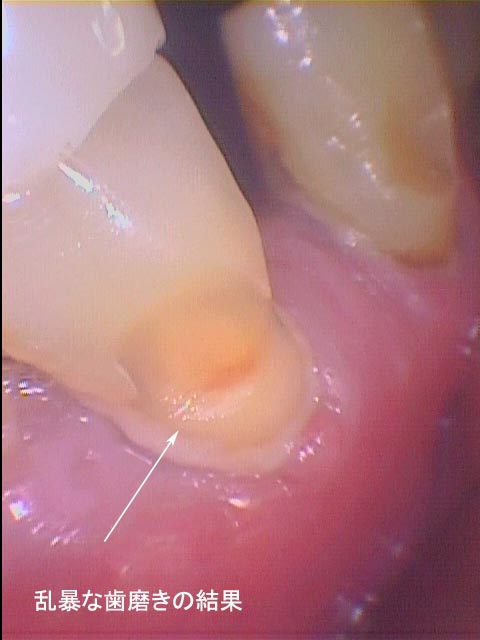

ブラッシングで歯周病は治ると指導され、動く歯を指で支えながらブラッシングを行ない定期的に受診。しかし、うがいの水もすごくしみ、歯の動揺のため咀嚼困難となりFDCを受診。

Phot―3.、Xray―1.からブラッシングによる歯の摩耗(黄矢印)が確認できる。

この症例も「ブラッシング教」信者の悲劇といえる。

自明のことであるが補助手段のブラッシングによって症状は一時的に改善するが

「歯周病が治癒」することはない。

現在、転院されてくる手遅れの患者さんを診ていますと日常的に行なわれている定期検査の在り方に多大な疑問を感じます。同様にブラッシング指導についても熱心な指導はよいとしても指導効果の検証がされていないために患者さんの歯の摩耗が多々みられます。